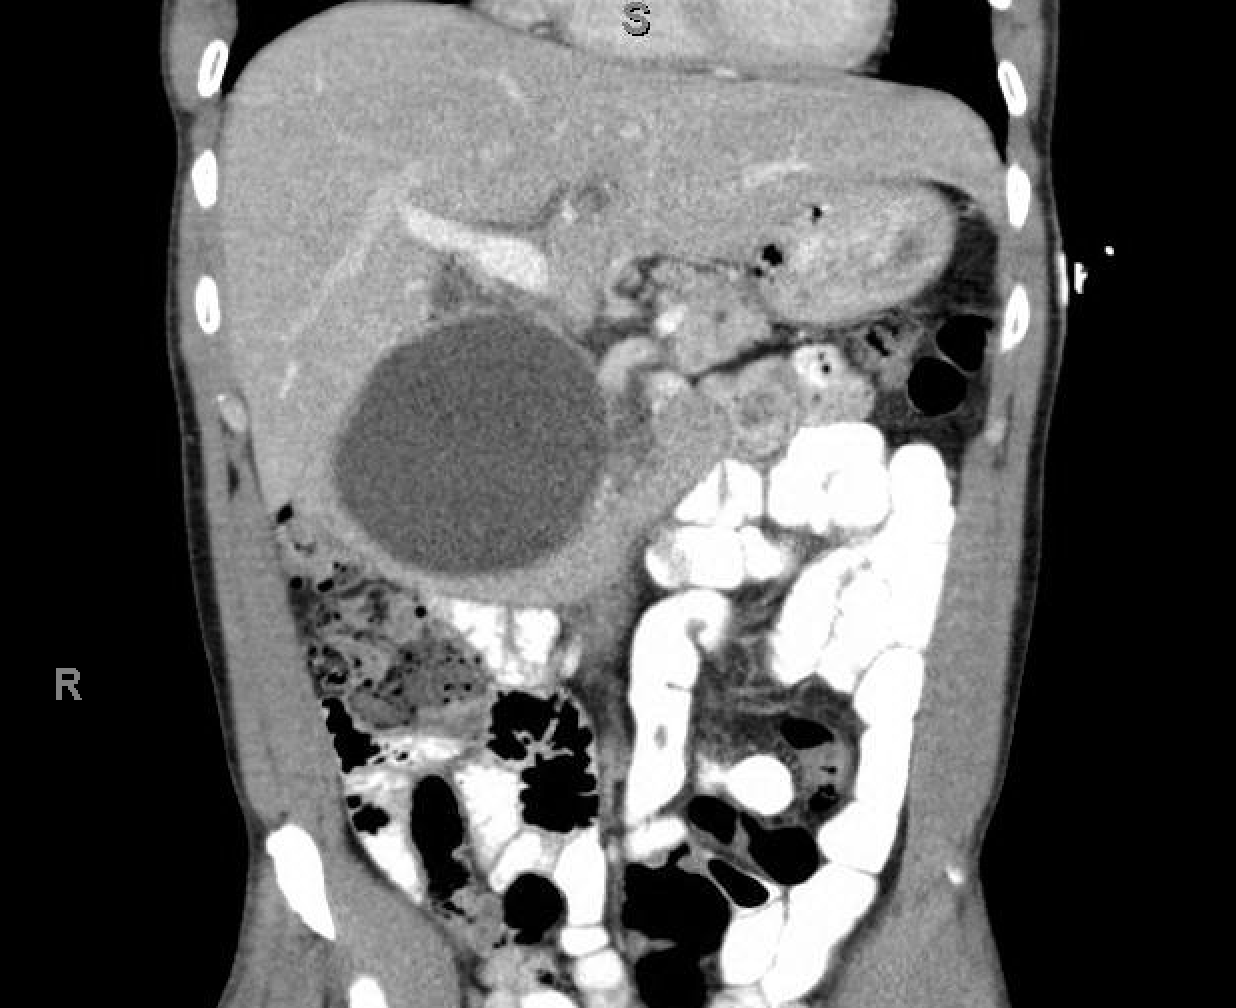

The providers were unsure. A CT scan of the abdomen was obtained to better define the mass. Here are some of the images:

The mass was thought to be either a large pancreatic pseudocyst, a low-grade cystic pancreatic neoplasm, or a duodenal duplication cyst.